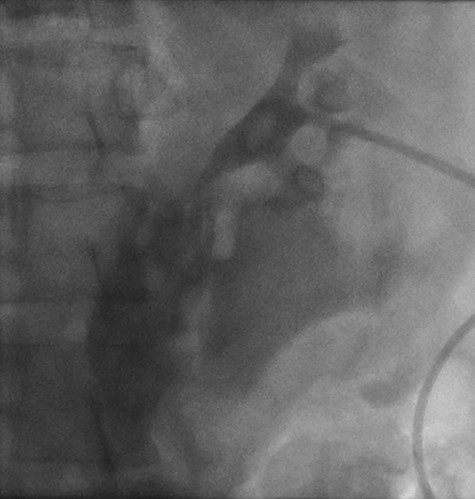

Right retrograde cystoscopy exhibiting extravasation of contrast.

Cystoscopy with retrograde pyelogram was performed by the urology team and this showed total disruption of the UPJ bilaterally with extravasation of contrast (Figs 3 and 4). She underwent bilateral interventional radiology nephrostomy tube placement. The definitive repair was planned for after pregnancy, but she required tube changes every 6 weeks. There was no fetal distress during her stay. She recovered well and was discharged after 5 days.